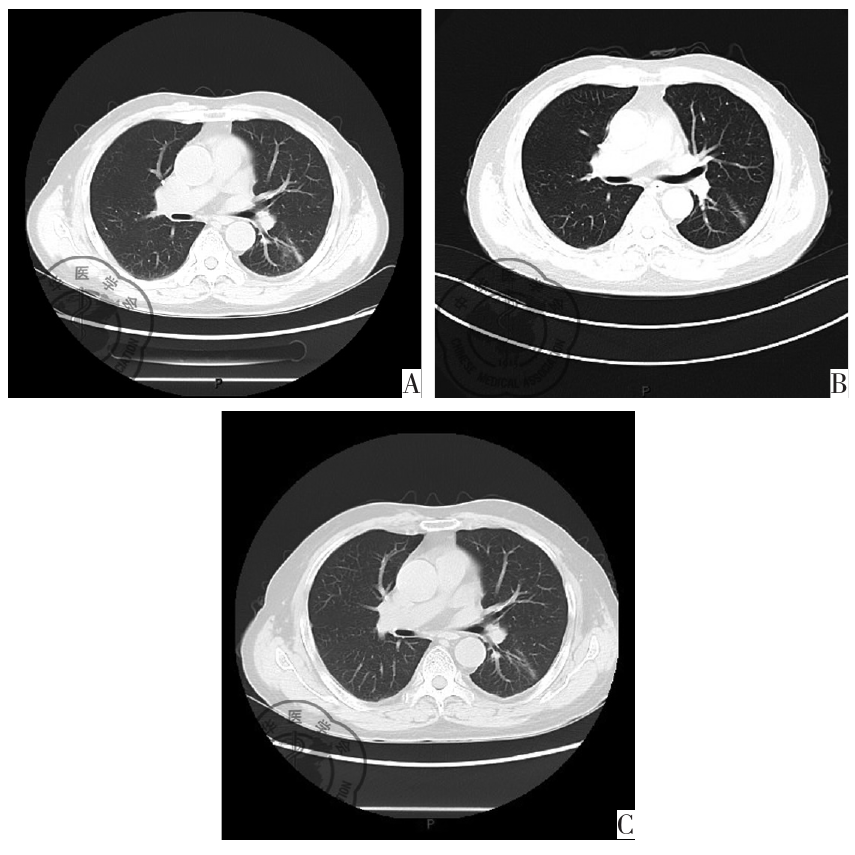

图1 2020-06肺部CT左下肺肿块影

图2 2020-07肺部CT左下肺肿块影较前吸收变小

图4 治疗后肺部CT图。注:A:治疗2个月肺CT左下肺肿块影消失,局部可见纤维密度增高影;B:治疗6个月肺CT左下肺局部少许密度增高影;C:治疗12个月肺CT左下肺局部少许密度增高影